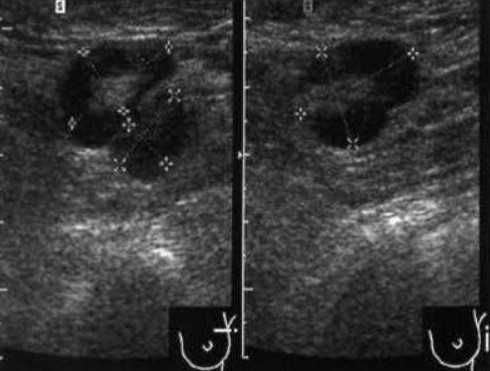

- Лучший диагностический признак на УЗИ - односторонние, овальные / эллиптические, слегка увеличенные, гипоэхогенные, дискретные лимфатические узлы (уровни II-V) у молодых азиатских пациенток

- Расположение. Задний треугольник шеи или внутренняя яремная цепь. Большинство на уровнях II и V. Односторонние изменения встречаются чаще, чем двусторонние

- Размер. Обычно 0,5-4,0 см (в среднем: 1,6 см), меньше лимфомных узлов

Ультрасонографические данные